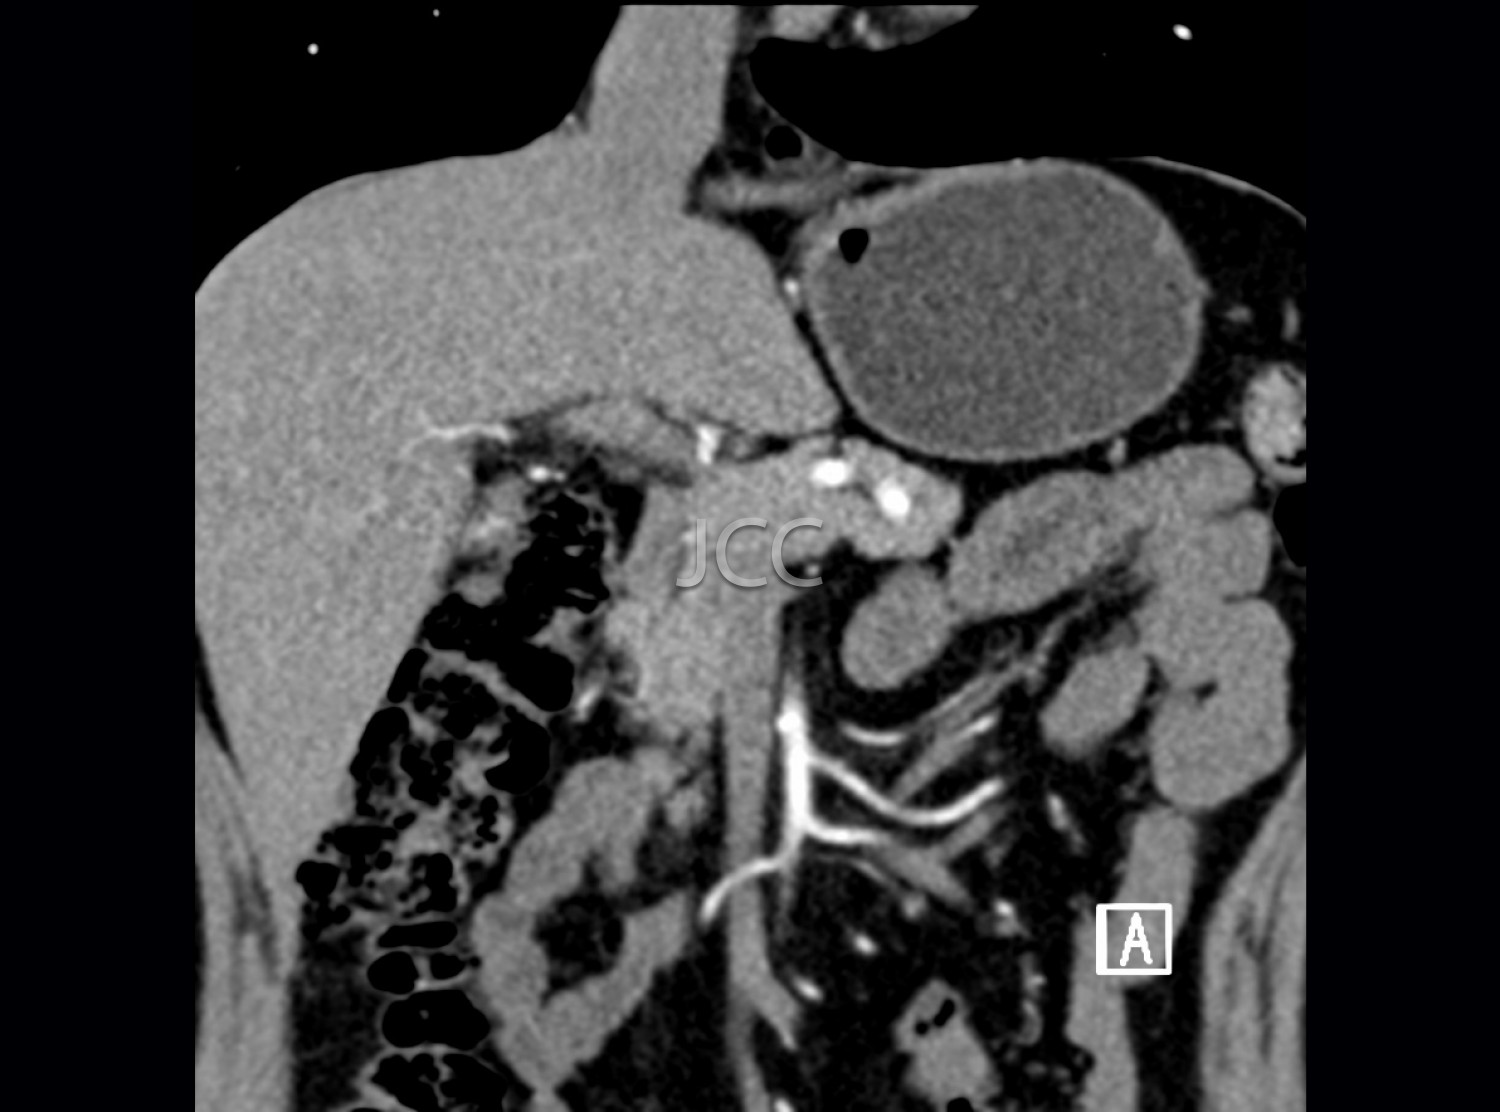

Computed Axial Tomography - Pancreatic CAT Scan

Computed Axial Tomography (CAT) - Dual Energy- 256 slices is a diagnostic technique that allows the evaluation of various parts of the human body, including the lungs, liver, pancreas, kidneys, heart, vascular structures and bone structures.